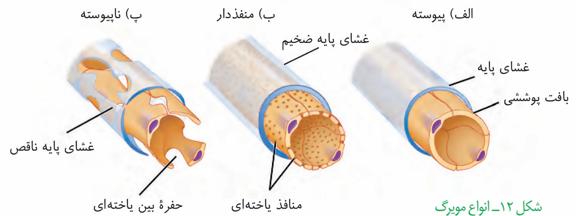

مویرگهای کلیه منفذدار هستند. پس ما هم کلافک و هم دور لولهای را منفذدار در نظر میگیریم.

گزینه «۳»: مویرگهای کلیه از نوع منفذدار هستند.